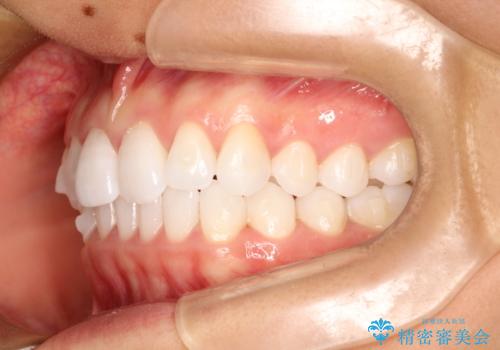

気になる前歯の歯並びをインビザラインで矯正

- 前歯の傾きと、ガタガタが気になるとのことで来院されました。

アスリートの方でしたので、競技に支障が少ないインビザラインで治療することとなりました。

前歯の傾きや高さをシミュレーションで患者様と確認しながら、歯並びを仕上げていきました。